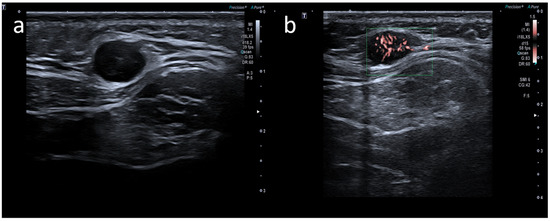

Atypical Sites of Lymphadenopathy after Anti-COVID-19 Vaccine: Ultrasound Features

- Cocco, G.; Pizzi, A.D.; Fabiani, S.; Cocco, N.; Boccatonda, A.; Frisone, A.; Scarano, A.; Schiavone, C. Lymphadenopathy after the Anti-COVID-19 Vaccine: Multiparametric Ultrasound Findings. Biology 2021, 10, 652. [Google Scholar] [CrossRef] [PubMed]